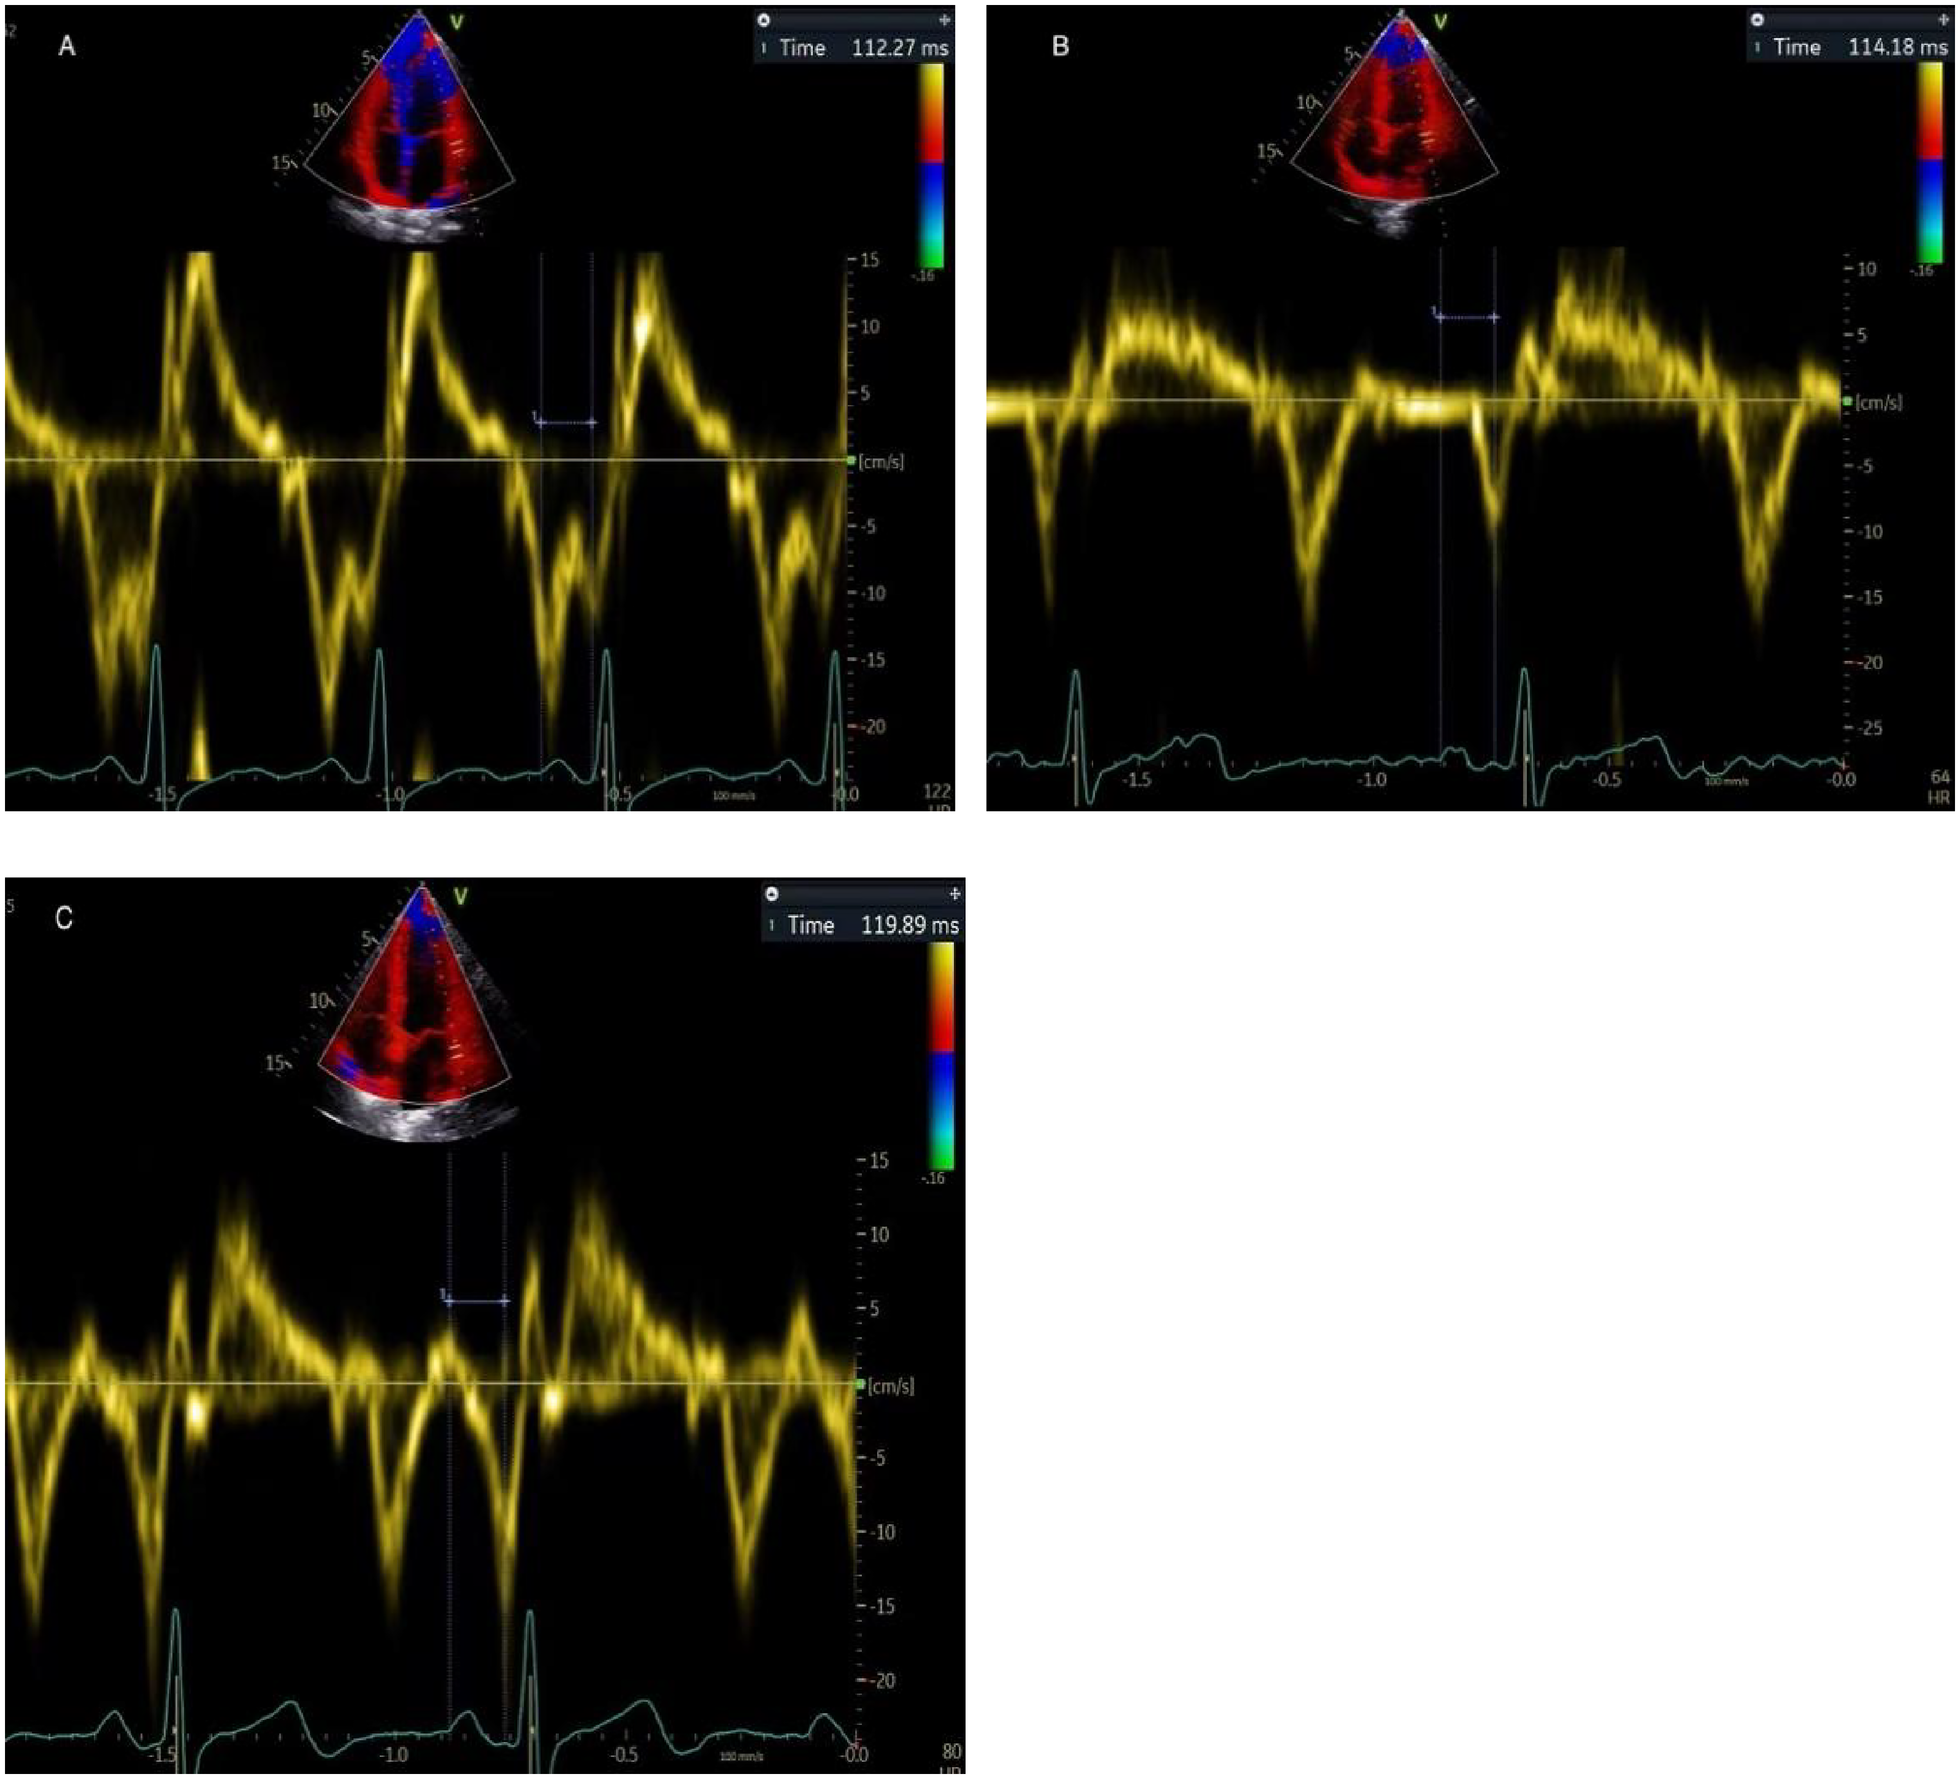

The PA-TDI duration was calculated using color-coded TDI imaging in the apical 4-chamber view (Figure 1). A fixed 8 mm × 8 mm region of interest was positioned on the lateral LA wall, immediately above the mitral annulus to trace mechanical activation of this region. The time interval from the beginning of the P-wave on the surface electrocardiogram to the peak of the A'-wave on the TDI tracing was used to measure the PA-TDI duration (14).

Figure 1

Depiction of measuring PA-TDI duration in the same patient. It is calculated using the interval between the beginning of the P-wave on the surface electrocardiogram and the peak of the A'-wave on the TDI tracing. (A) early pregnancy, (B) middle pregnancy, (C) late pregnancy.